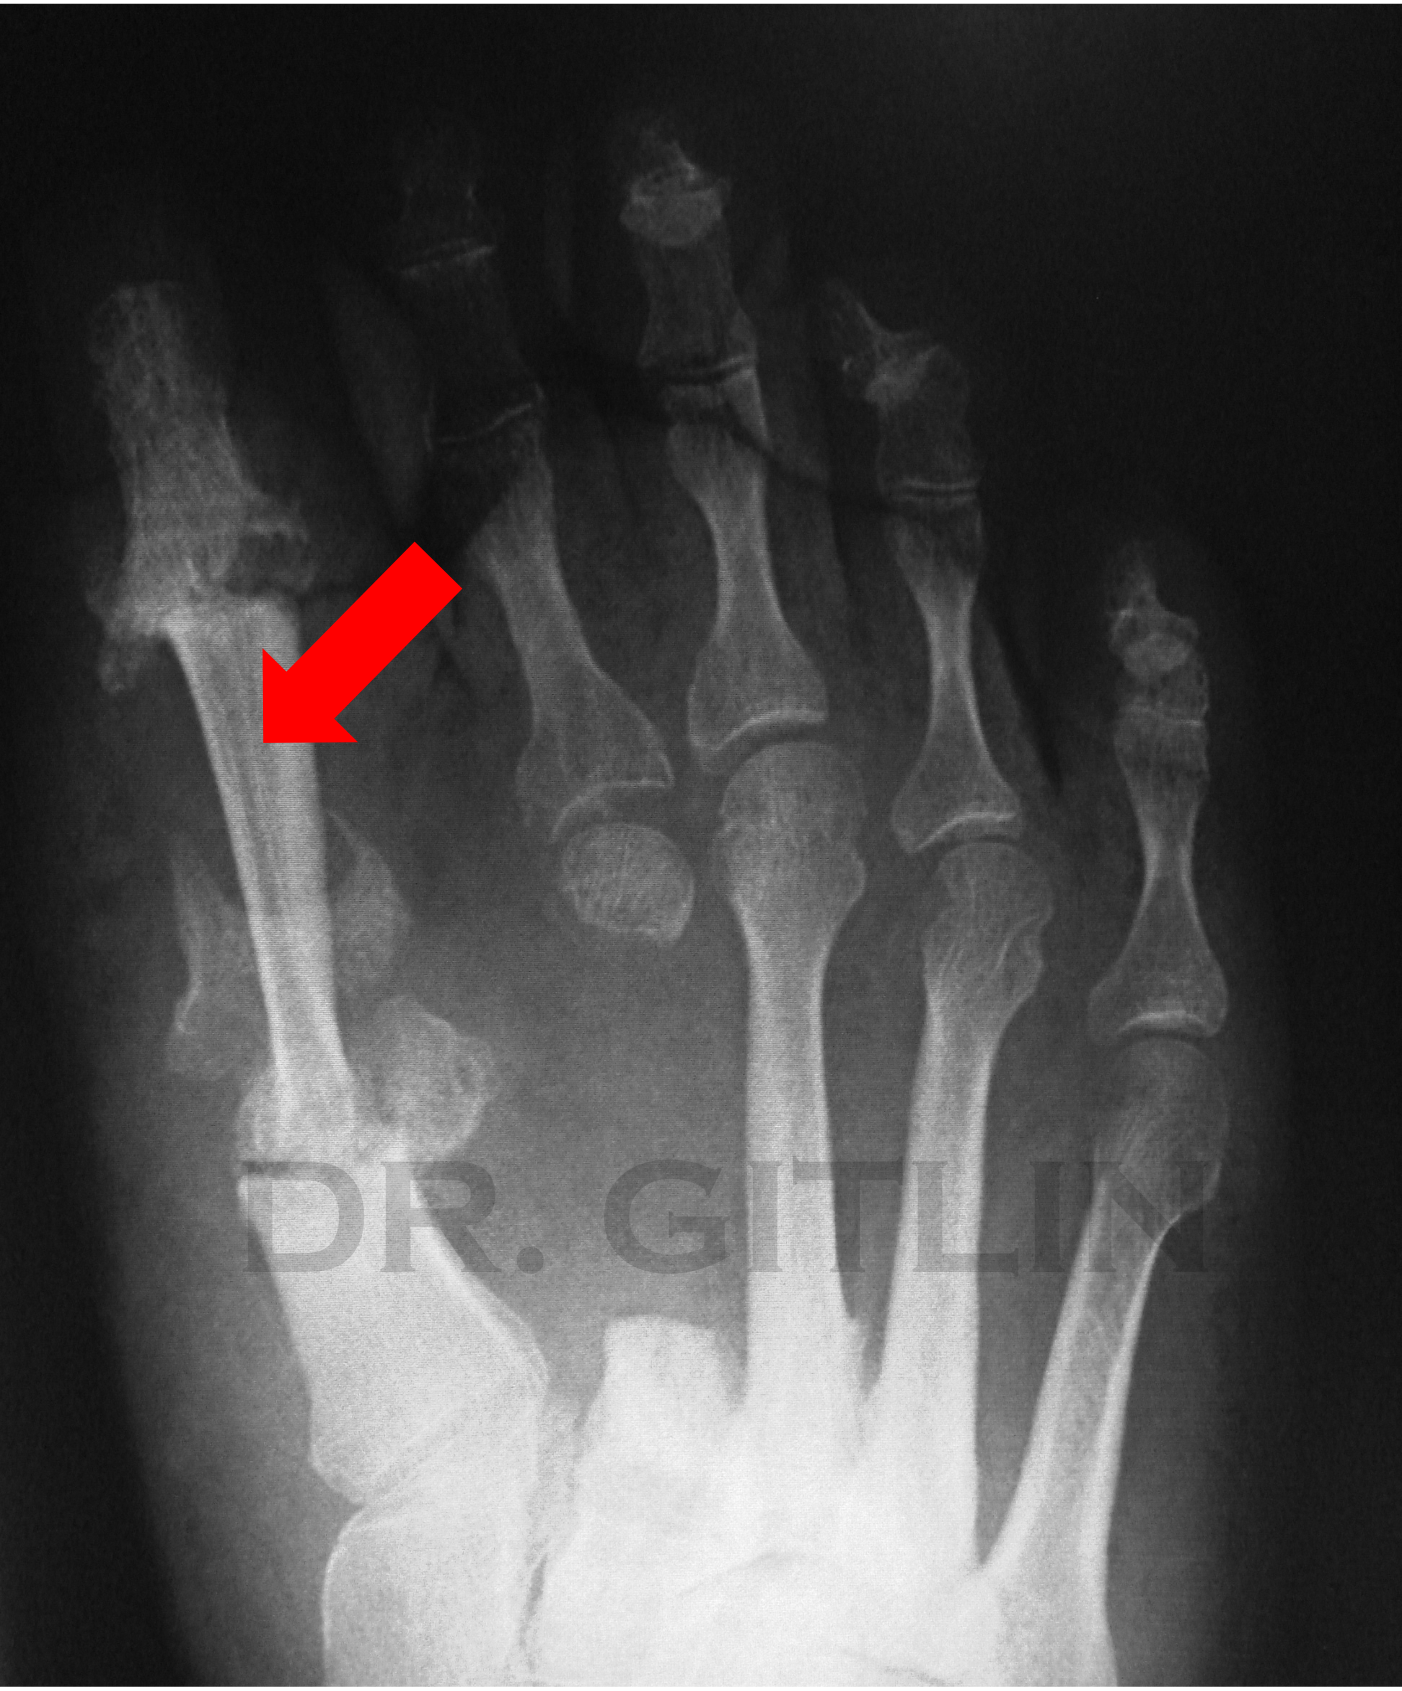

We removed the implant and all the bad bone around it. and then we cut out the bone right next to it. Also called a metatarsal that attaches to the second toe. And we moved that bone into the space of the first metatarsal bone. We decided the first metatarsal was more important for stability of the foot so we sacrificed the second metatarsal. The RED arrow in the pictures points to the second metatarsal so you can follow where it came from and where it ended up. We used an external fixator that is also pictured here to hold the bones together and allow the patient to walk immedialty after surgery.

X-ray of a human foot showing a fracture in the metatarsal bone, indicated by a red arrow.